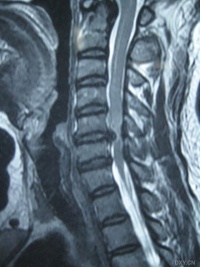

颈椎间盘突出的影像学检查[编辑 | 编辑源代码]

磁共振成像(MRI) 可直接显示颈椎间盘突出部位、类型及脊髓和神经根受损的程度,为颈椎间盘突出症的诊断、治疗方法选择及预后提供可靠依据。MRI对颈椎间盘突出症诊断的准确率远远大于CT和CTM。在中央型和旁中央型颈椎间盘突出症中可显示清晰影像。

颈椎间盘突出症的诊断主要依靠症状、体征和影像检查(CT、MRI核磁共振等),特别是核磁共振在确诊颈椎间盘突出方面具有重要意义。颈椎间盘突出可根据颈椎间盘病理改变的影像学特征分为颈椎间盘变性、膨出、突出、脱出、游离等主要类型。人的颈椎由于特殊的应力关系往往出现多个节段的同时病变,这与腰椎间盘突出症略有不同。诊断多无困难,诊断依据: